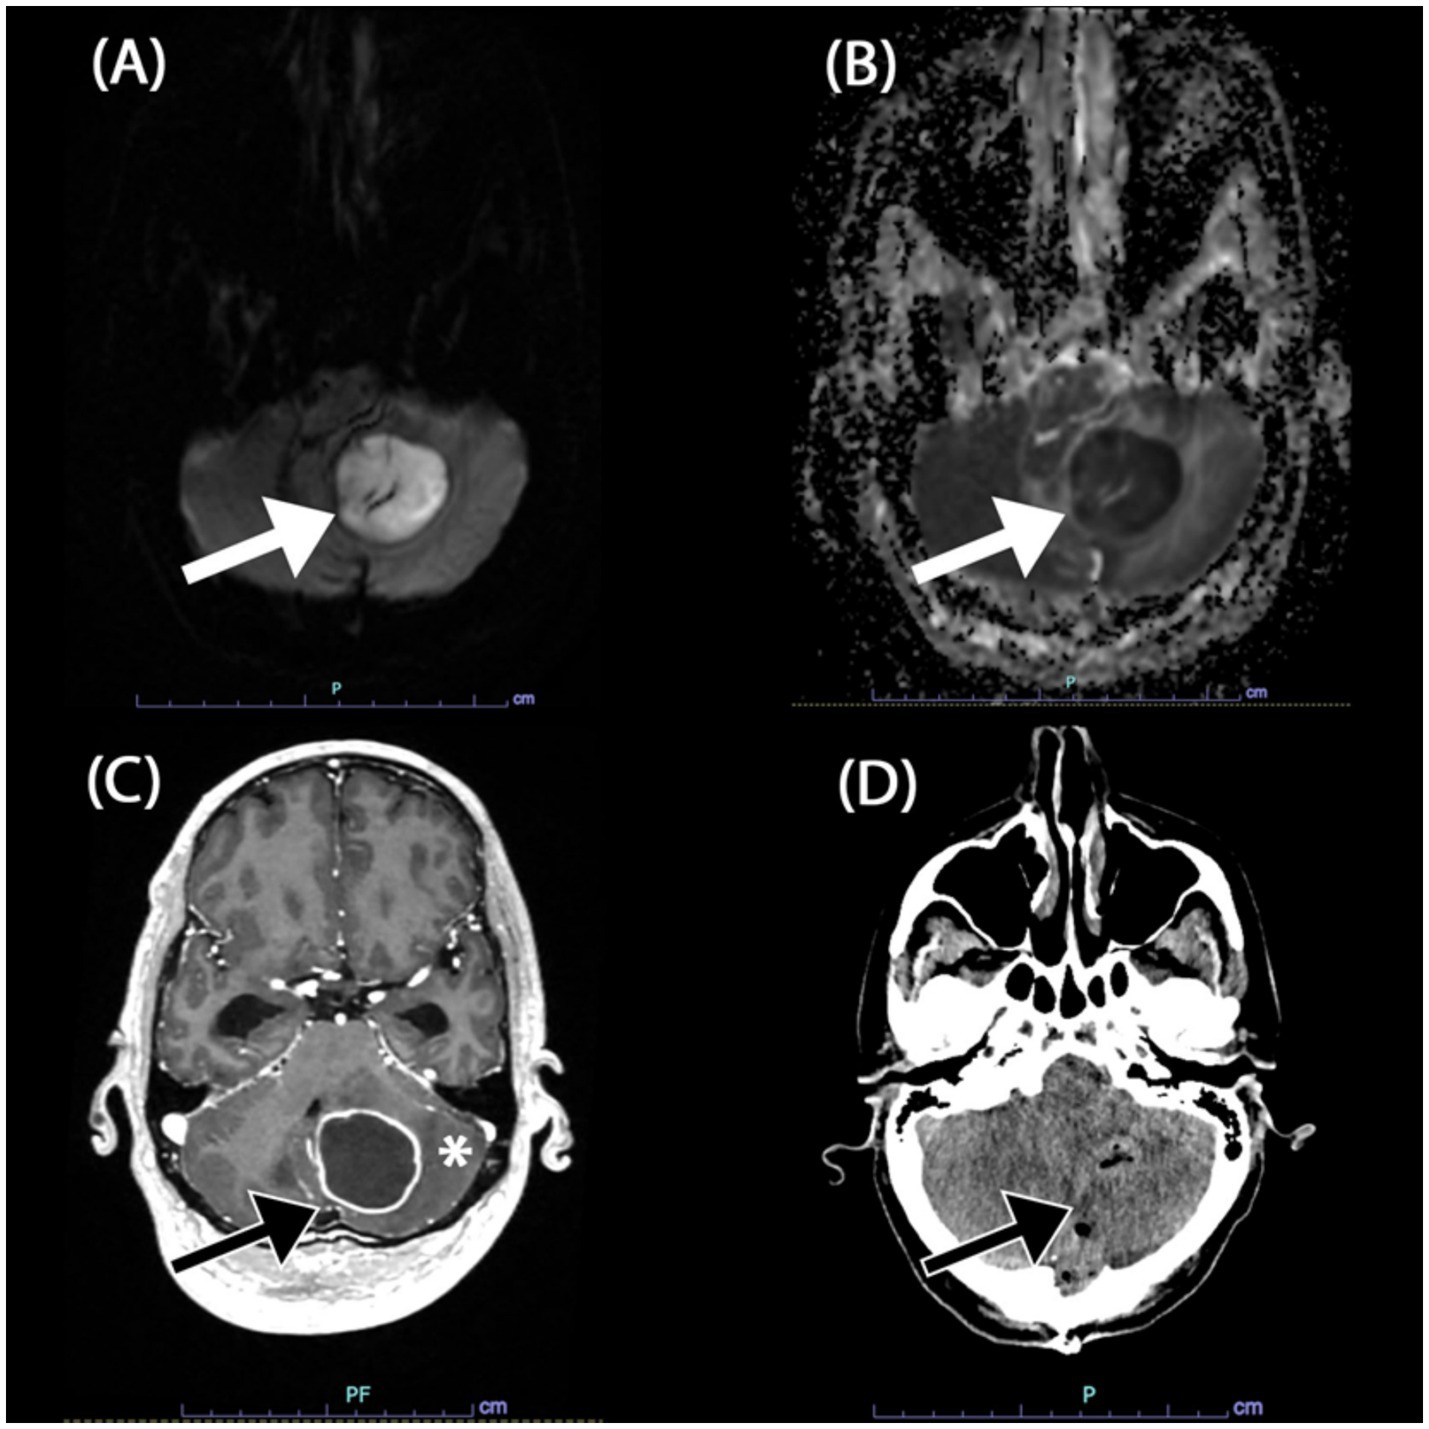

The initial symptoms of altered consciousness and ataxia were attributed to a presumed posterior circulation ischemic event. A magnetic resonance imaging (MRI) revealed a large, 3.4 × 3.5 × 3.2 cm mass in the left cerebellum (Figures 1A–C), which exhibited restricted diffusion and rim enhancement. The mass was exerting a significant effect on the fourth ventricle, resulting in obstructive hydrocephalus. The leading differential diagnoses at this juncture were CNS lymphoma and a cerebellar abscess. Diffusion-weighted imaging (DWI) was also performed (Figures 1A,B) and showed findings that were most suggestive of an abscess.

Figure 1. Magnetic resonant imaging (MRI) of the brain in axial views. (A,B) DWI b1000 and ADC showed restricted diffusion of the mass in the left cerebellum (white arrow). (C) Post-gadolinium contrast T1-weigted image revealed rim enhancing component of the mass (black arrow) associated with surrounding oedema (*). Note the compression onto the fourth ventricle causing obstructive hydrocephalus (not shown). (D) Post-operative non-contrasted computed tomography (CT) of the brain in axial view revealed the post operative air locules (black arrow) in the left cerebellum without bleed and resolution of fourth ventricle compression.

The patient’s postoperative course was managed in the intensive care unit (ICU). An extensive evaluation for other concurrent infections, including serial blood cultures and a comprehensive panel of serologies, was negative. A non-contrasted CT brain did not show any significant bleed and resolved obstructive hydrocephalus (Figure 1D). A CT scan of the chest, abdomen, and pelvis revealed findings consistent with ventilator-associated pneumonia but no definitive primary focus of nocardiosis.